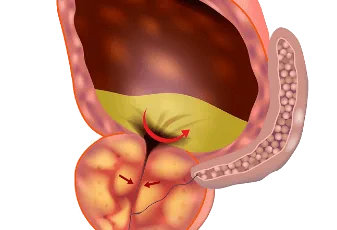

כריתת כיס מרה

כריתת כיס מרה - המדריך עם כל המידע הרפואי והמעודכן כיס המרה מכיל נוזלי מרה, שיש להם תפקיד בתהליך העיכול (ובפרט בעיכול של שומנים). בתהליך היצירה והשחרור של נוזלי המרה, נאגרים לעיתים נוזלי המרה בצירוף מלחים ומתקשים לכדי אבנים בכיס המר